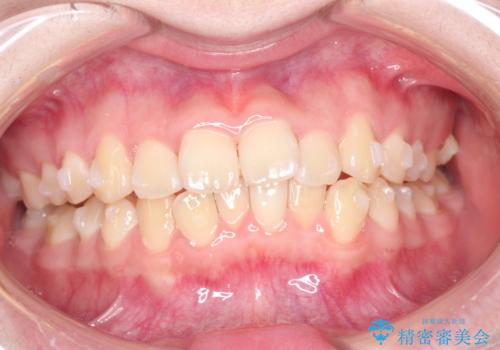

なるべく通院回数を減らして矯正したい インビザラインでのガタガタ矯正

- 上下の歯並びを治したいとのことで来院されました。

受験生ということもあり、なるべく通院回数を減らしての矯正を希望されたので、インビザラインで治療をすることにしました。

ワイヤー矯正が1か月に1回程度来院が必要なのと比較すると、2-3か月に1回の来院でもよいので(症例によります)、通院回数を減らすことができて、患者様の負担を減らすことができます。